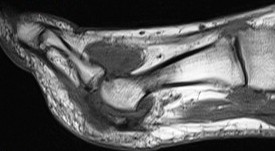

Figure 4 for case Gout arthritis ( RID3567 )

Figure 4

Even infiltrating his Tibialis Anterior.